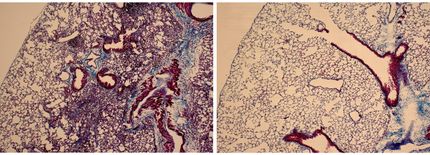

Fibrosis is a perfidious disease. Scar tissue increasingly and irreversibly replaces healthy tissue. The result is that organs such as the lungs, liver or kidneys lose function. In the case of the lungs, more than 80 percent of fibrosis are only detected at a late stage – when the tissue is already extensively scarred and can no longer be saved. Life expectancy for patients with lung fibrosis is then frequently no more than three to five years.

The probe is as nondescript as it is effective: to the naked eye, it appears as a white powder that dissolves in water. When it encounters tissue – e.g. in the form of a biopsy – or bodily fluids in which LOX is active, it begins to fluoresce in a blue colour. “The crucial factor is that we can not only prove the presence of the enzyme but also that it is actually active,” Antoniazzi emphasises.

His aim is to use this probe to create a kind of early warning system. Because although LOX is also active in healthy tissue, the quantities involved are only very small. When fibrosis sets in, activity rises rapidly. “If we can detect this rise in good time, doctors can intervene at an early juncture – before the tissue is irreparably damaged,” Antoniazzi explains.

There is still a long way to go until clinical application. “At the beginning, we tested the probe primarily on tissue samples,” Antoniazzi continues. But biopsies are usually only conducted when the disease is already advanced. For that reason, he shifted his focus at the start of his fellowship to liquid samples such as blood serum. “If we could validate the probe for blood serum, that would represent a major step towards early diagnostics.”